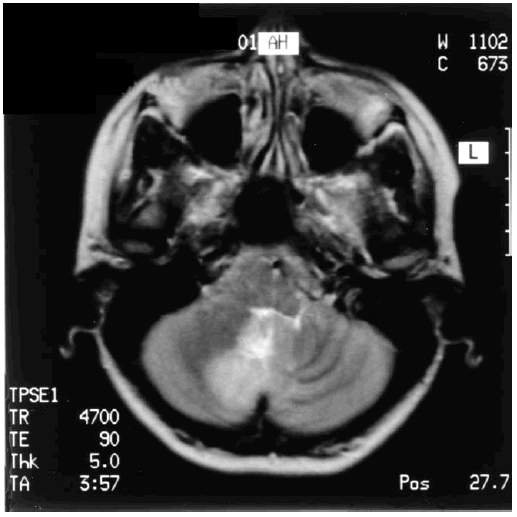

Опухоли лобной доли могут в начале проявиться только изменениями поведения. Одним из ранних симптомов может быть психическое расстройство, проявляющееся общей апатией, потерей интереса к окружающим, заторможенностью, неопрятностью или, наоборот, повышенной возбудимостью, агрессивностью, снижением критики, внимания, памяти, интеллекта, дурашливостью, склонностью к плоским, сальным шуткам. Выдающийся канадский врач Пенфилд отметил, что «мы не знаем комнаты, где прячется сознание»; то же можно сказать об интеллекте. Пациенты с опухолью лобной доли нередко производят впечатление людей, у которых произошло значительное снижение интеллекта, сопровождающееся психическими нарушениями. Следует согласиться с мнением о том, что эти расстройства не являются результатом внутричерепной гипертензии, поскольку развитие ее наблюдается при лобных опухолях в меньшей степени и на более поздних стадиях, чем при новообразованиях другой локализации, которые реже сопровождаются поражением высших корковых функций [145]. Нарушения когнитивных функций могут выявляться и при опухолях ствола головного мозга. При обследовании 101 пациента с первичными, вторичными и околостволовыми опухолями (55 мужчин и 46 женщин) в возрасте 16–75 лет расстройства высших корковых функций выявлялись у 9,9 % больных [179]. Авторы отмечают, что снижение критики, эйфория, снижение памяти обычно наблюдались у пациентов с окклюзионной гидроцефалией. При этом расстройства памяти преобладали у больных с околостволовыми опухолями, преимущественно области таламуса. У пациентов с опухолями ствола возможно развитие патологического смеха, нарушений поведения, что объясняют тесными связями с височной долей, изменениями серотонинергической нейротрансмиссии [204]. Как отмечалось, когнитивные расстройства могут развиваться у пациентов с поражениями мозжечка. На рис. 12.1 представлена МРТ головного мозга пациентки 38 лет с опухолью намета мозжечка, у которой, наряду с мозжечковой симптоматикой, выявлялись умеренные когнитивные нарушения, регрессировавшие через семь месяцев после нейрохирургической операции. Благодаря успехам клинической неврологии и достижениям современной нейрорадиологии стали возможными ранняя диагностика опухолей головного мозга и направление таких пациентов в нейрохирургические отделения.

Рис. 12.1. МРТ головного мозга пациентки с опухолью намета мозжечка с УКР